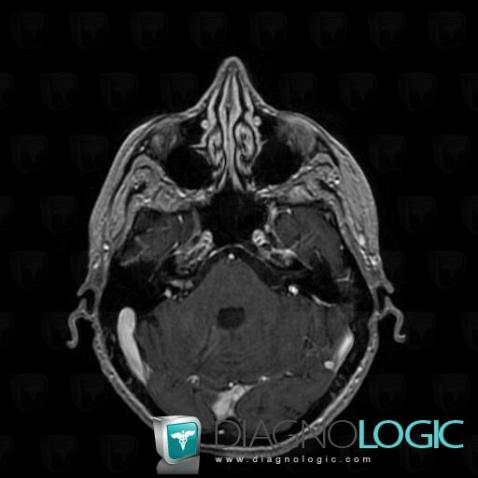

Les images ci-dessous illustrent ce dossier pour les diagnostics Carcinose méningée, Méningite carcinomateuse, pour les modalités (IRM)

Voici les informations spécifiques à l'image clé ci dessus:

- Diagnostic Carcinose méningée, Localisation(s) Autres nerfs craniens, comportant les gammes Lésion des nerfs craniens

Voici les informations spécifiques à l'image clé ci dessus:

- Diagnostic Méningite carcinomateuse, Localisation(s) Espaces peri cérébraux infratentoriels, comportant les gammes Réhaussement méningé diffus

Voici les informations spécifiques à l'image clé ci dessus:

- Diagnostic Carcinose méningée, Localisation(s) Autres nerfs craniens, comportant les gammes Lésion des nerfs craniens

Voici les informations spécifiques à l'image clé ci dessus:

- Diagnostic Carcinose méningée, Localisation(s) Hypophyse et région parasellaire, comportant les gammes Lésion de la tige pituitaire